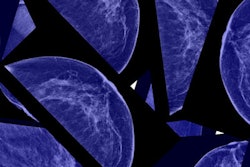

Breast cancer screening attendance in Switzerland has hit a new low, despite expanding regional mammography screening programs. Several breast radiologists have blamed antiscreening information and the debate surrounding the pros and cons of breast cancer screening.

Swiss researchers analyzed data from nationwide representative health surveys. Led by Dr. Lukas Fenner, a senior research scientist at the Institute of Social and Preventive Medicine, University of Bern, the researchers spotted a drop of more than 7% in mammography use from 2007 to 2012.

The researchers found that the use of any mammography in the past 12 months declined from 19.1% in 2007 to 11.7% in 2012. The decline was more pronounced in regions with a long-standing program or no cantonal breast cancer screening program; levels remained relatively stable in regions with a recently introduced program.

The researchers also found that opportunistic screening dropped from 12.0% in 2007 to 6.2% in 2012, whereas the use of programmatic mammography remained stable at 3.1%. Use of any mammography was higher in women ages 50 to 69, those residing in a region with a systematic screening program in place, and those having a private hospital stay insurance, but it was not associated with education level and non-Swiss citizenship.